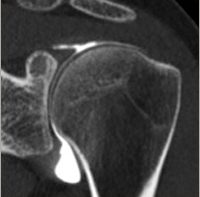

Scanner

L’image tomodensitométrique est obtenue à partir des mêmes contrastes fondamentaux que la radiologie conventionnelle (rayons X, air, graisse, eau, os, contrastes artificiels). Le mode d’acquisition des images est cependant extrêmement différent : un faisceau de rayons X et une couronne de détecteurs tournent autour du corps du patient et enregistrent une série d’histogrammes correspondant aux profils d’atténuations des tissus de la coupe examinée suivant plusieurs projections. Après l’acquisition, les images scannographiques sont traitées pour obtenir des coupes dans des plans anatomiques différents et aussi des reconstructions appelées tridimensionnelles car elles donnes une image en relief. Dans la pathologie de l’appareil locomoteur, le scanner sert essentiellement à l’analyse osseuse notamment les fractures.

Arthro-Scanner

On injecte dans l’articulation un produit de contraste iodé avant le scanner afin de pouvoir analyser en plus des structures osseuses, les cartilages, les ménisques au genou, les tendons de la coiffe des rotateurs ou le bourrelet glénoïdien à l’épaule, le bourrelet cotyloïdien à la hanche ou rechercher des corps étrangers intra-articulaires.

Le produit de contraste est injecté par le radiologue en salle de radiographie et le scanner est réalisé dans la foulée. Lorsque l’injection est réalisée par des radiologues expérimentés elle est peu douloureuse et le geste est très rapide. Le patient n’est piqué qu’une fois. Le produit de contraste peut entraîner une réaction allergique dans de très rares cas. Ainsi, chez les patients allergiques, on prescrit un traitement antihistaminique à prendre trois jours avant l’examen.